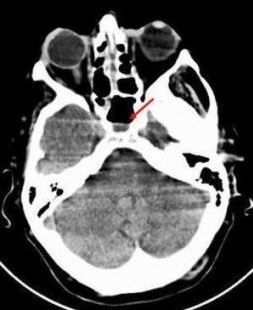

A 67-year-old woman presented with delirium resulting from diabetic ketoacidosis and complained of headache, facial pain, nasal congestion, left eye pain, and blurry vision. Her past medical history was significant for type 2 diabetes mellitus. A CT scan of her head shows general swelling of the turbinates with maxillary congestion and air-fluid level on the ethmoidal sinus. The diagnosis was rhinocerebral mucormycosis.